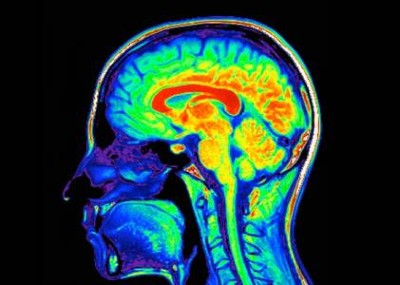

In the study, scientists identify a brain–immune circuit that exacerbates cardiovascular pathology during a heart attack. They identified neurons in the vagus nerve that relay signals between the heart and the brain, which in turn activates immune and inflammatory responses and causes widespread damage to the heart. Blocking this pathway improved outcomes after a heart attack in mice, which could pave the way for developing new therapies.

Earlier research has shown that the vagus nerve — a key pathway that connects the brain to many other organs — sends signals to the brain after a heart attack.

These post-heart attack signals from the heart to the brain result trigger the sympathetic nervous system — the body’s ‘fight or flight’ response — he explains. The increased sympathetic response then causes inflammation in the heart tissues and impairs cardiac function, which can lead to heart failure.

“The root cause of the problem is signals going from the heart to the brain,” says Shivkumar. But the key cells and molecular pathways that underlie these processes have remained unclear.